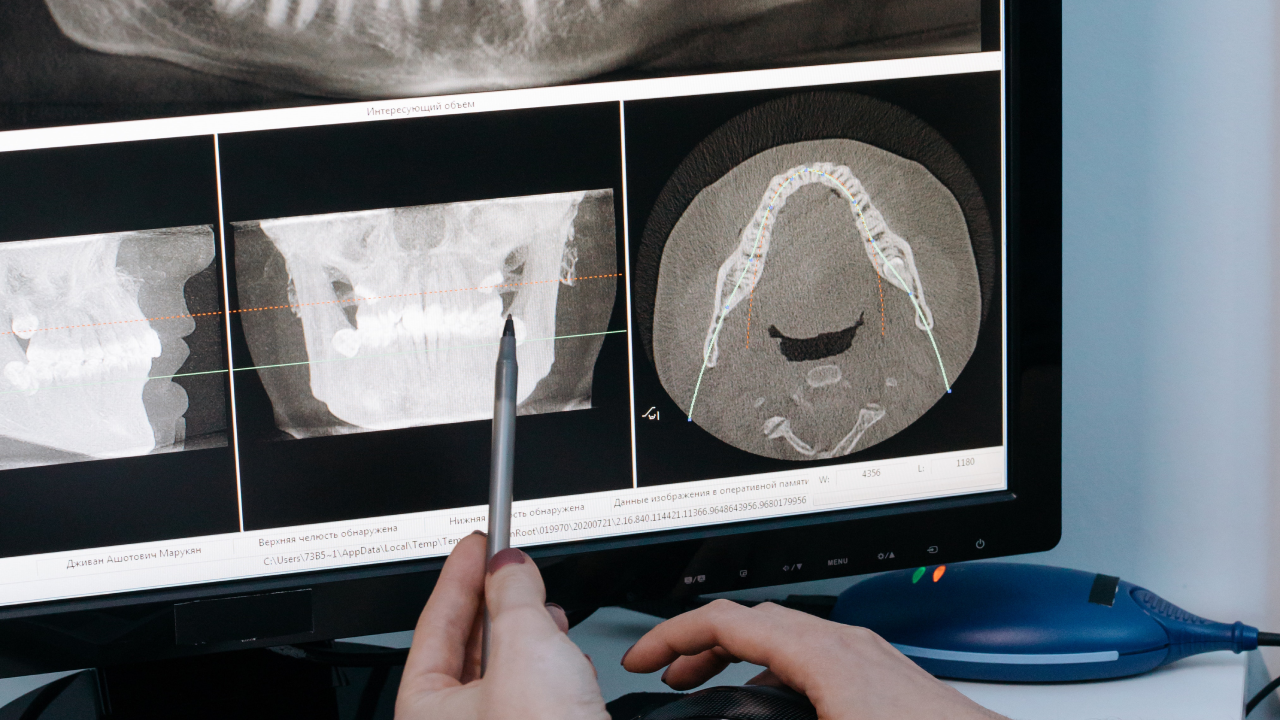

Gli impianti dentali in Albania sono una soluzione artificiale che sostituisce la radice dei denti mancanti o danneggiati. Consistono in un supporto in titanio che viene inserito nell’osso mascellare o mandibolare come base per la protesi dentale.

Le soluzioni All-on-4, All-on-6 e All-on-8 sono la risposta definitiva per chi vuole recuperare una dentatura completa fissa in tempi rapidi. Con pochi impianti strategicamente posizionati, è possibile ottenere denti fissi permanenti in soli 3-5 giorni, anche in caso di perdita ossea avanzata.

Una procedura chirurgica che aumenta la quantità di osso nella mascella, creando le condizioni ideali per il posizionamento degli impianti.

Utilizza materiali biocompatibili o tessuti del paziente stesso per stimolare la crescita naturale dell’osso nella zona interessata.

La soluzione per la mancanza totale di osso nella mascella superiore. Gli impianti vengono ancorati all’osso zigomatico, eliminando la necessità di innesti ossei.